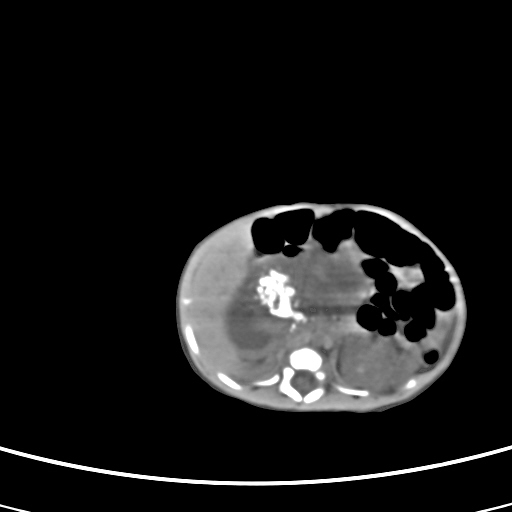

患儿,男性,出生后2天,在胎儿时b超已发现病变,患儿一般情况可。因病变部位偏向于右侧肾上腺区,目前考虑为神经母细胞瘤,不知各位能否支持。

病灶内未见明显脂肪密度。

反对定位在右肾上腺区的说法,那么神经母细胞瘤也可以暂时不予考虑。请看下图:

下面这幅图中,似乎可以见到肿瘤的薄包膜,其后与右肾之间的又是什么东西呢?这关系到肿瘤的定位、定性。我考虑病灶是位于肝十二指肠韧带内的畸胎瘤可能性比较大。请各位老师仔细看一下:

病灶巨大,位于右侧肾上腺区,与周围组织分界欠清,内见不规则钙化影,无明显脂肪组织,首先考虑神经母细胞瘤,但畸胎瘤不能排除。